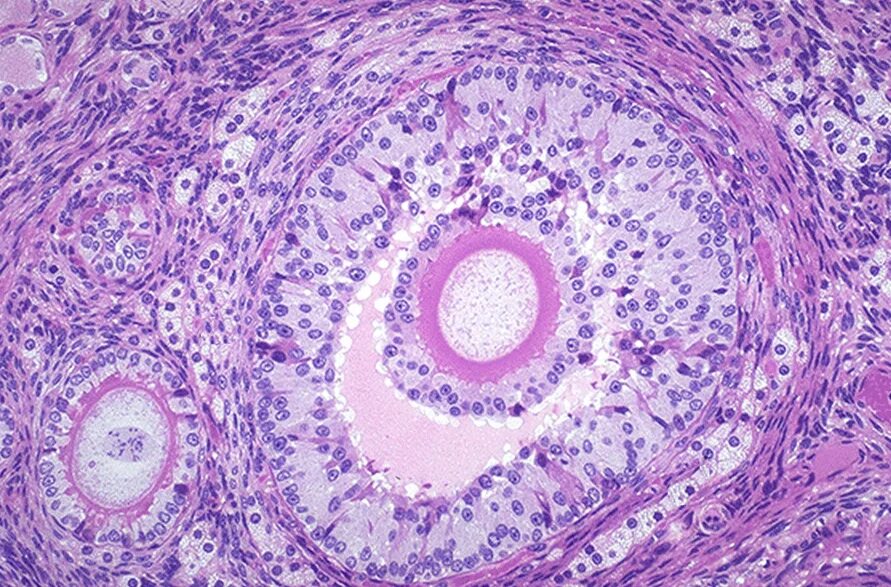

Что показала гистология замершей